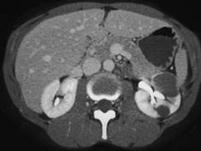

问题 女,35岁,请根据所示图像,选择最可能诊断 ( )

选项 A、左侧肾盂旁囊肿 B、左侧囊性肾癌 C、左侧高密度肾囊肿 D、左侧肾积水 E、左侧单纯性肾囊肿

答案 C